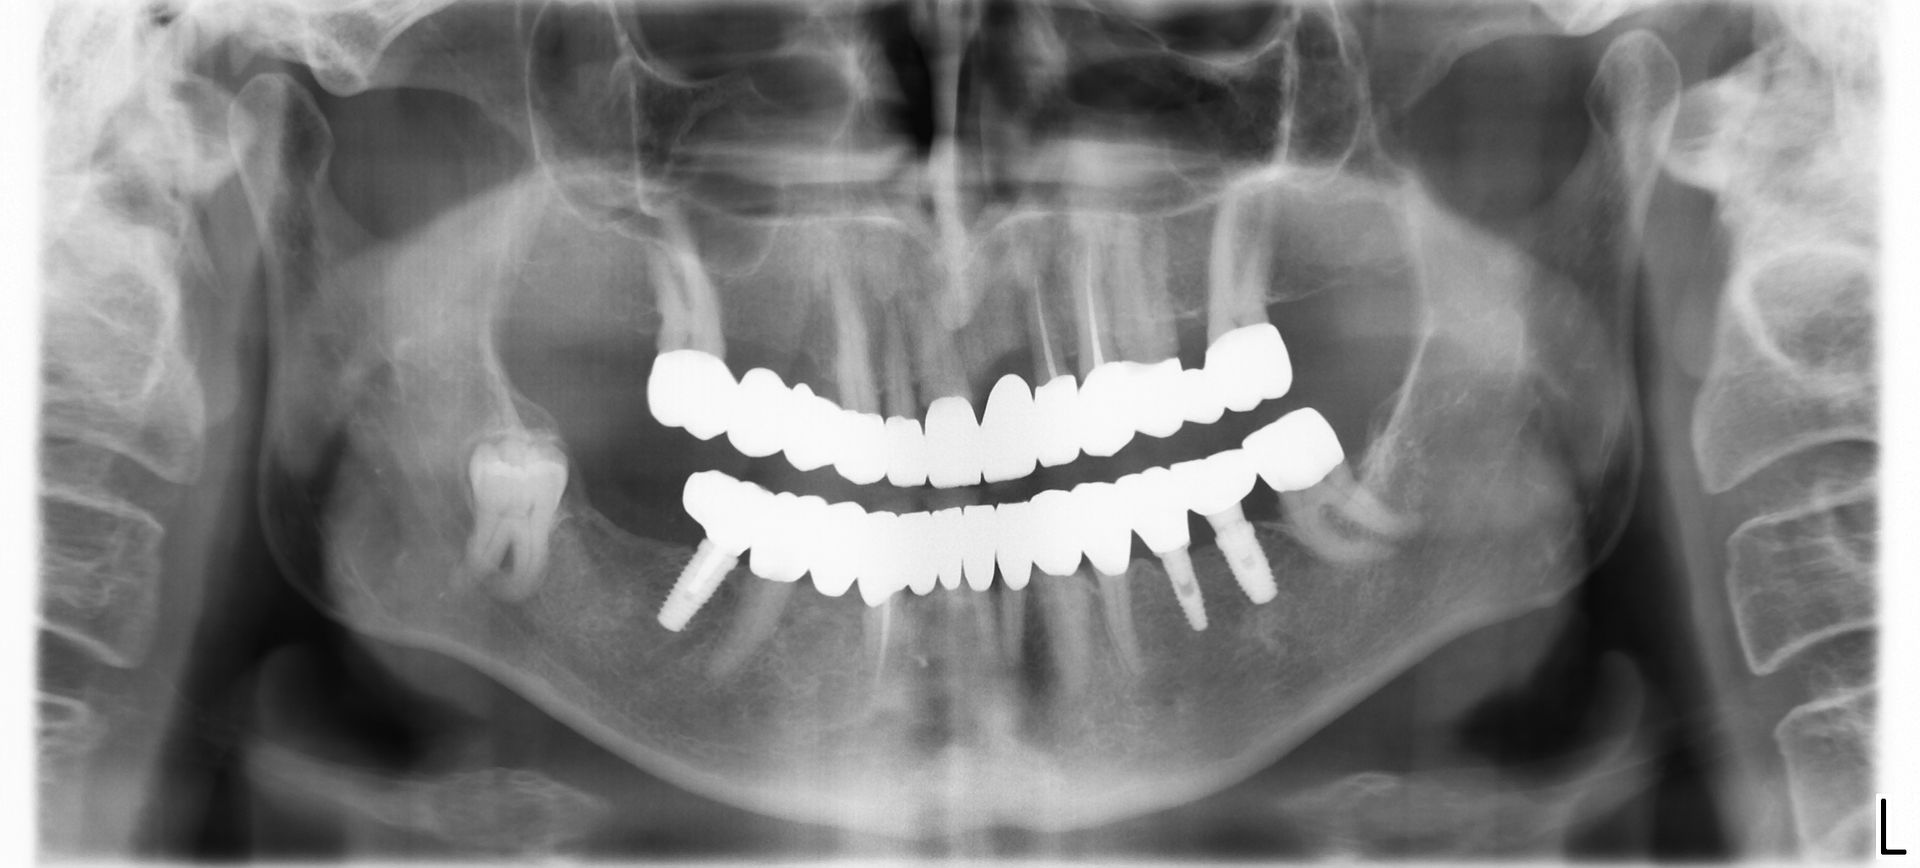

Una volta eliminate le cause che hanno portato alla perdita di uno o più denti e valutato lo stato di salute generale del paziente, si procede con la pianificazione dell'intervento su TAC, che fornisce al medico informazioni circa la qualità e la quantità dell'osso. In base alla condizione clinica dei tessuti di partenza e alla zona da riabilitare, viene scelta la tecnica chirurgica più idonea, tradizionale o a carico immediato.

Questa procedura, eseguita da professionisti con esperienza specifica, consente di ripristinare le condizioni ideali per il posizionamento implantare e ottenere una riabilitazione stabile e duratura. Per garantire estetica, comfort e funzionalità, prediligiamo

riabilitazioni fisse.

Il nostro obiettivo è restituire un sorriso naturale e armonioso attraverso protesi stabili e integrate, ricorrendo alla

protesi mobile solo quando non esistono alternative valide.Le soluzioni fisse Columbus, in particolare, offrono: